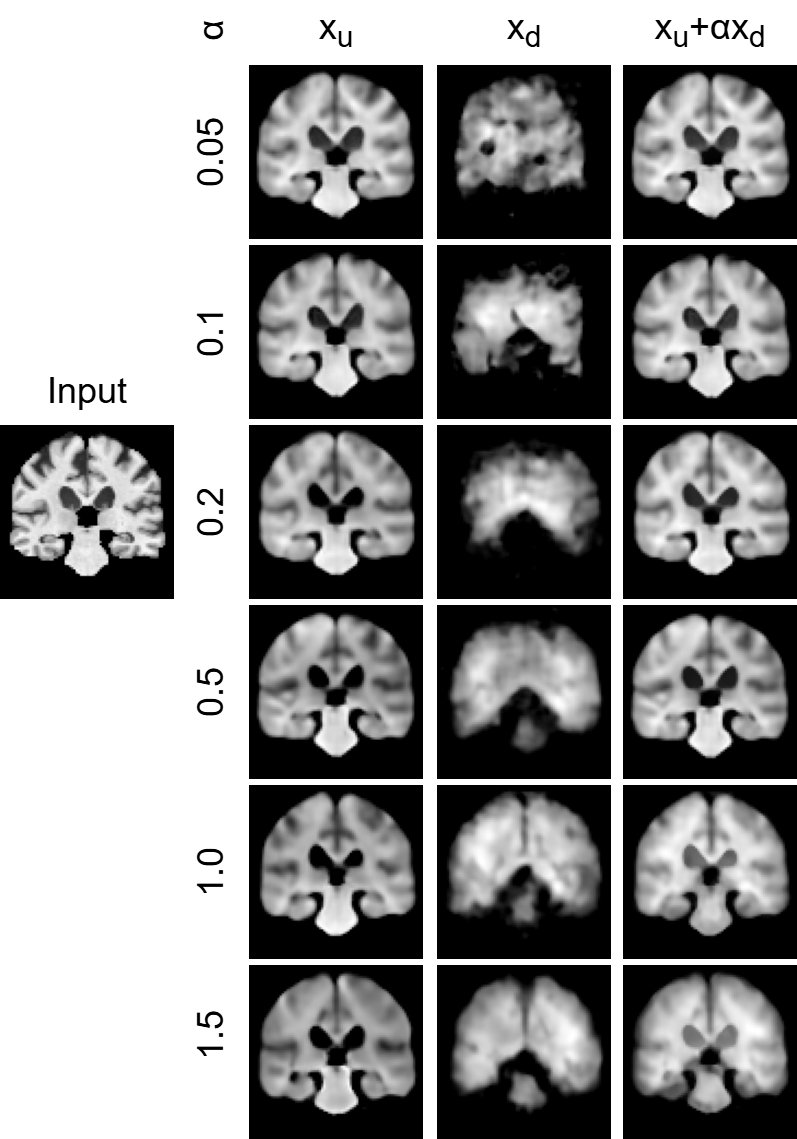

III-D Impact of hyperparameter

We compared how each result changed during the training of PL-SE-ADA by varying the value of in . The value of was varied across the following settings: 0.05, 0.1, 0.2, 0.5, 1.0, and 1.5.

IV-C Impact of hyperparameter

Fig. 4 visualizes the reconstructed images obtained by varying the weighting parameter , while Table III summarizes the reconstruction error, disease classification accuracy, and domain classification accuracy for each value of . As increases, the reconstructed images become progressively more whitish, with the regions derived from expanding. This observation suggests that increasing the contribution of domain-specific information during reconstruction results in visual content that becomes more localized to domain-related variations. By comparing reconstruction accuracy, disease classification accuracy, and domain classification accuracy, it is considered that provides the best balance between overall performance and interpretability.